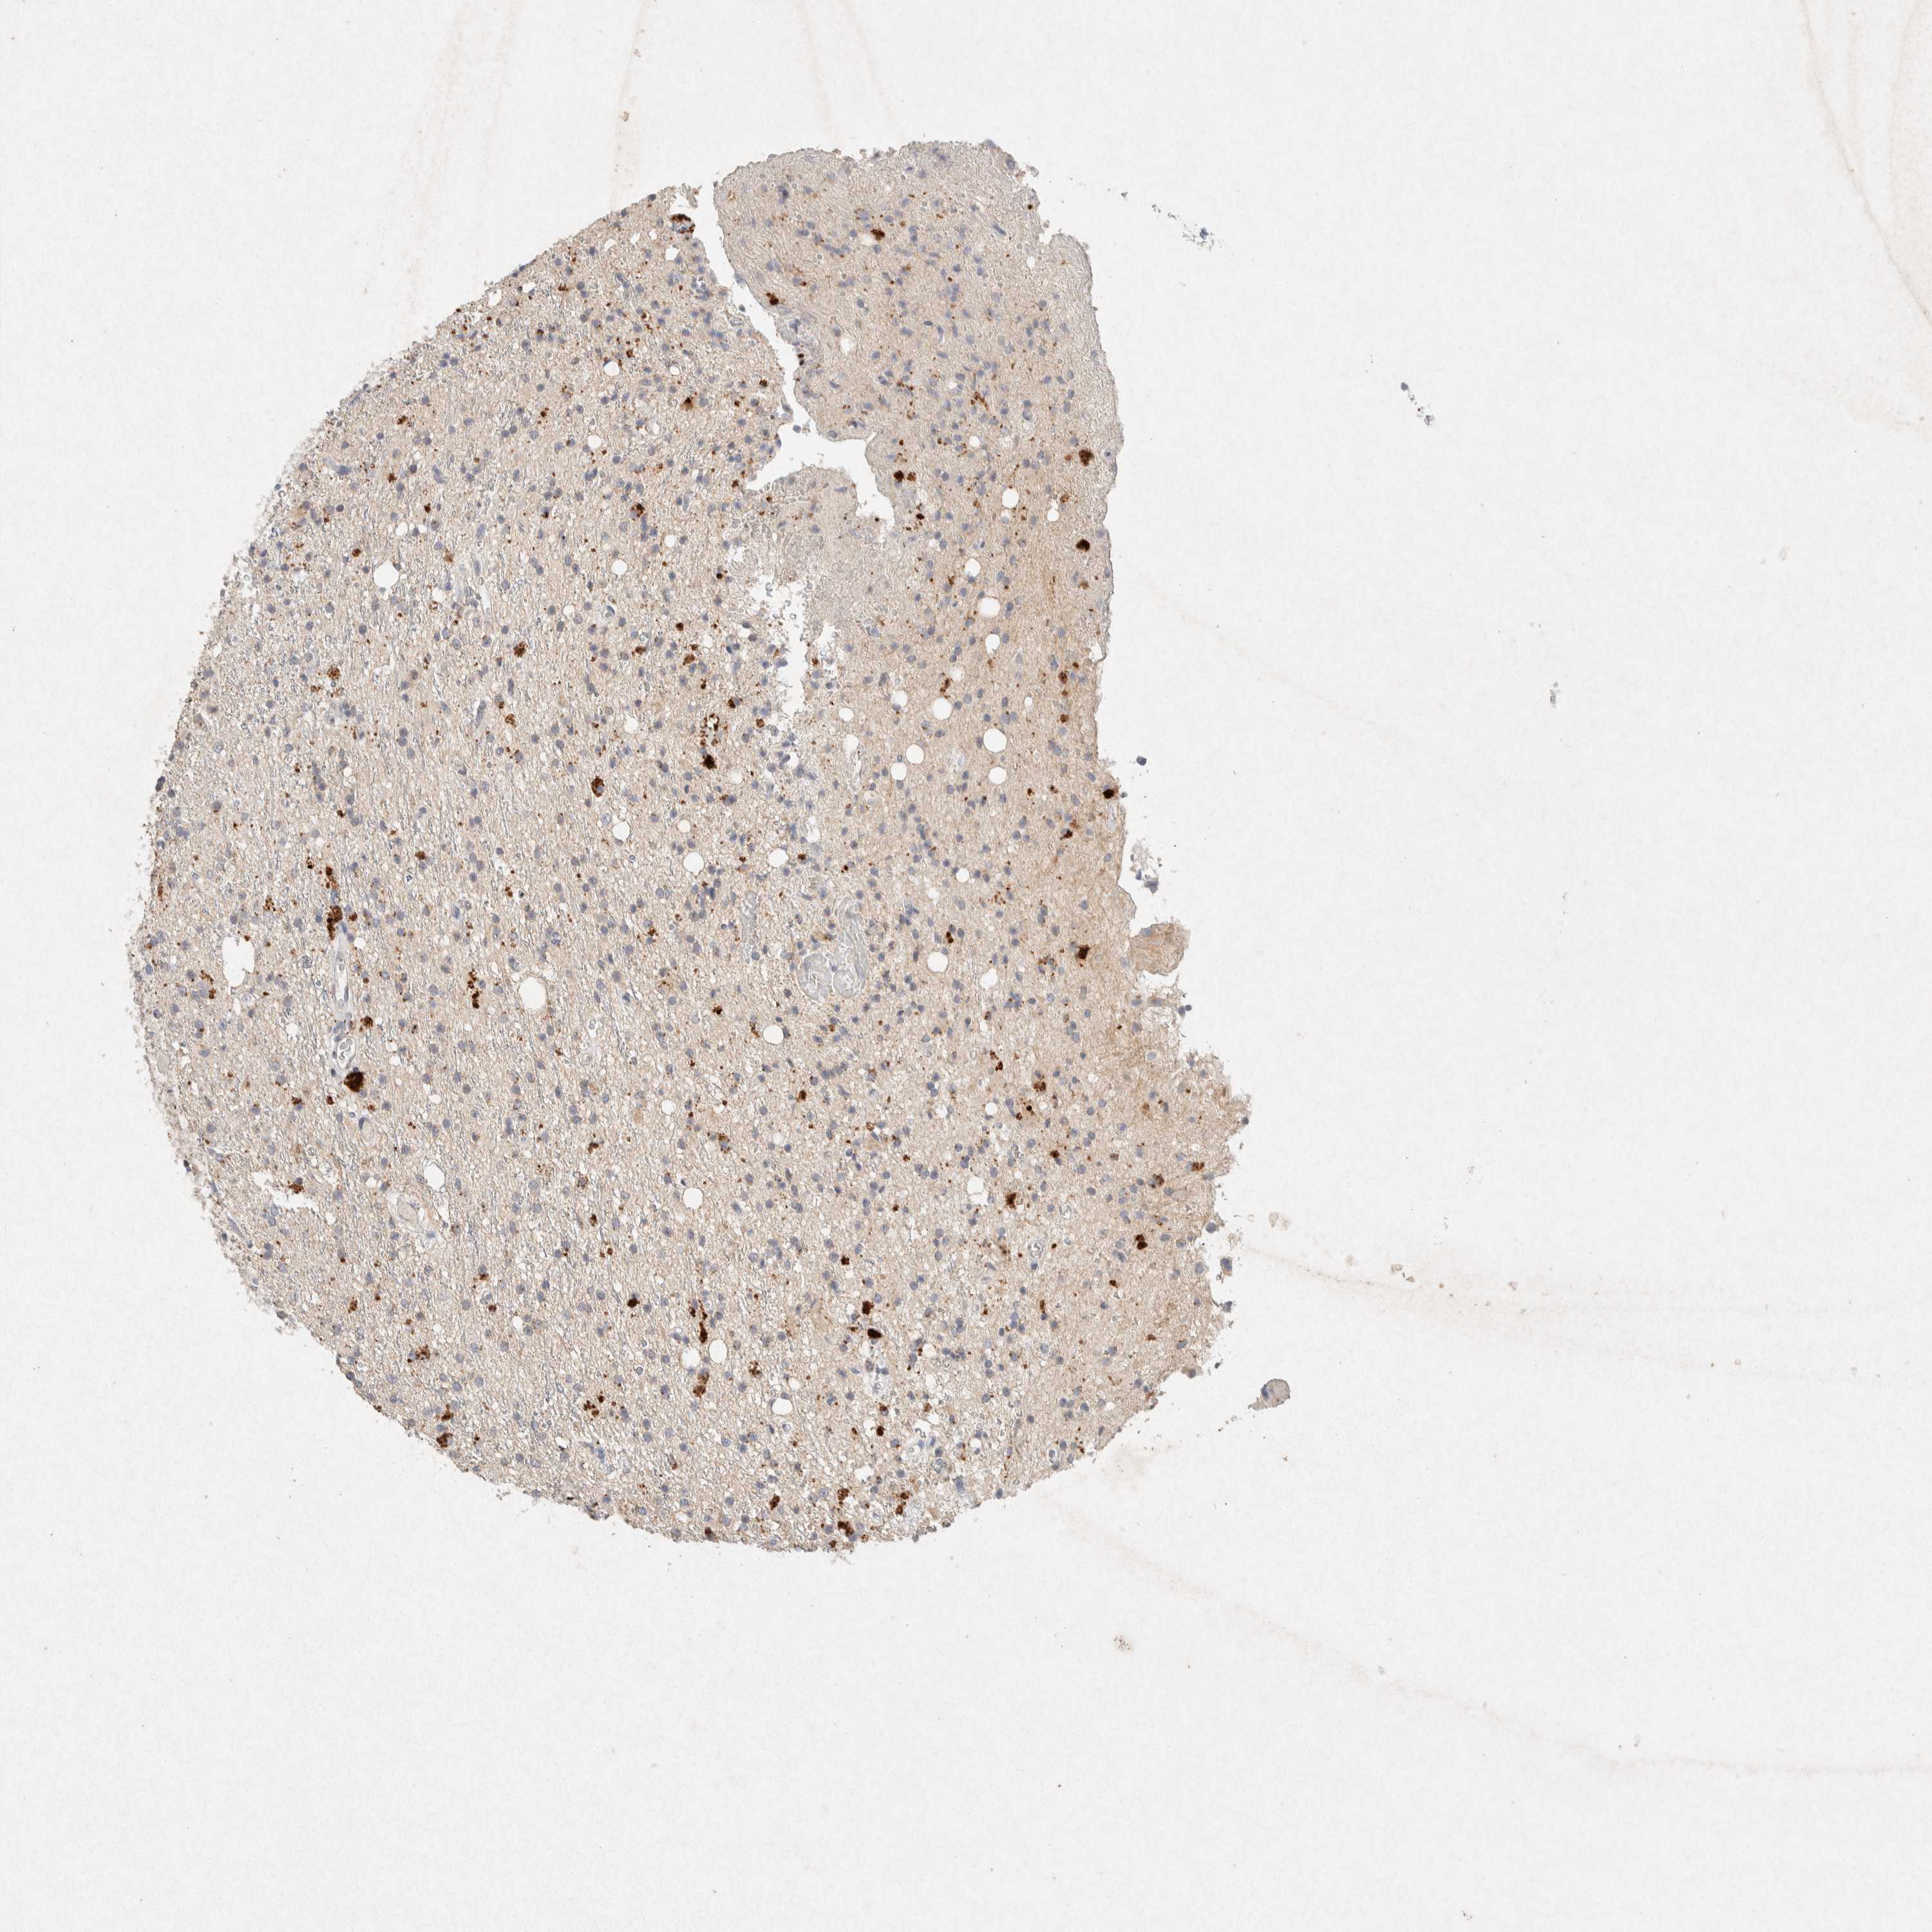

GLIOMA - Protein expressioni

A mouse-over function shows sample information and annotation data. Click on an image to view it in a full screen mode. Samples can be filtered based on level of antibody staining by selecting one or several of the following categories: high, medium, low and not detected. The assay and annotation is described here.

Note that samples used for immunohistochemistry by the Human Protein Atlas do not correspond to samples in the TCGA dataset.

Antibody stainingi

Antibody staining in the annotated cell types in the current human tissue is reported as not detected, low, medium, or high, based on conventional immunohistochemistry profiling in selected tissues. This score is based on the combination of the staining intensity and fraction of stained cells.

Each image is clickable and will lead to virtual microscopy that enables deeper exploration of all samples and also displays staining intensity scores, fraction scores and subcellular localization as well as patient and tissue information for each sample.

Antibody HPA042141

Antibody CAB022449

Staining

High

Medium

Low

Not detected

Intensity

Strong

Moderate

Weak

Negative

Quantity

>75%

75%-25%

<25%

None

Location

Nuclear

Cytoplasmic/membranous

Cytoplasmic/membranous,nuclear

Glioma, malignant, High grade

Glioma, malignant, Low grade